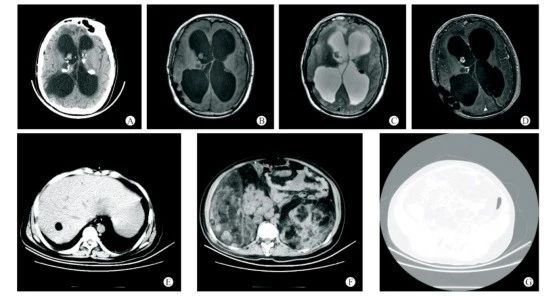

患者有癲癇并發(fā)育遲緩,9年前有雙側(cè)側(cè)腦室室管膜瘤切除史。A-D:雙側(cè)室管膜下多發(fā)結(jié)節(jié)樣鈣化灶,右側(cè)側(cè)腦室內(nèi)軟組織結(jié)節(jié);E:肝內(nèi)錯構(gòu)瘤;F:雙腎巨大錯構(gòu)瘤;G:椎體及雙側(cè)髂骨多發(fā)骨質(zhì)硬化。